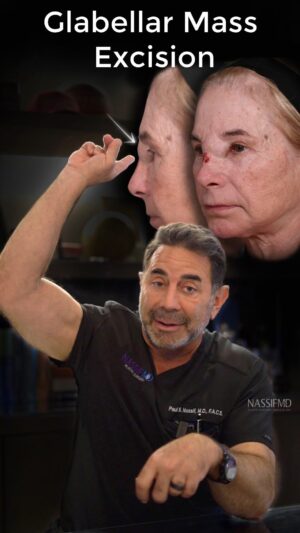

8.2K Likes – Paul Nassif Instagram

Caption : ⚠️ Warning: Do Not Inject Filler Into Your Glabella! Not only can it cause skin necrosis, which means the skin dies, but it can even cause blindness or other problems. My patient, Linda, developed this big mass, which you can see in the video above. FDA approved filler doesn’t usually cause this type of reaction, so we didn’t exactly know what was going on until we went into the OR. By doing a modified Lynch procedure, where we made incisions on the sides of the nose and dissected out the mass of tissue, we figured out what it was. The tissue ended up being what we call a foreign body reaction. Her body created the mass because it didn’t accept whatever was injected into her face. Here are Linda’s results after only 1-month, but they’ll continue to improve as swelling will decrease over the next three to four months! If you would like to treat the glabella, @nassifmedical recommends using Botox or a laser treatment instead! Trusted with Faces Worldwide® _____________________________________________ ☎️☎️ Call us at: 1 (310) 275-2467 💌💌 Email us at: [email protected] #nassifmedical #nassifmd #filler #botched #botchedfiller #glabella #facialplasticsurgery #beforeandafter #results #modifiedlynchprocedure #plasticsurgeon #cosmeticsurgery #facialplasticsurgery #face #tt #transformationtuesdayLikes : 8173